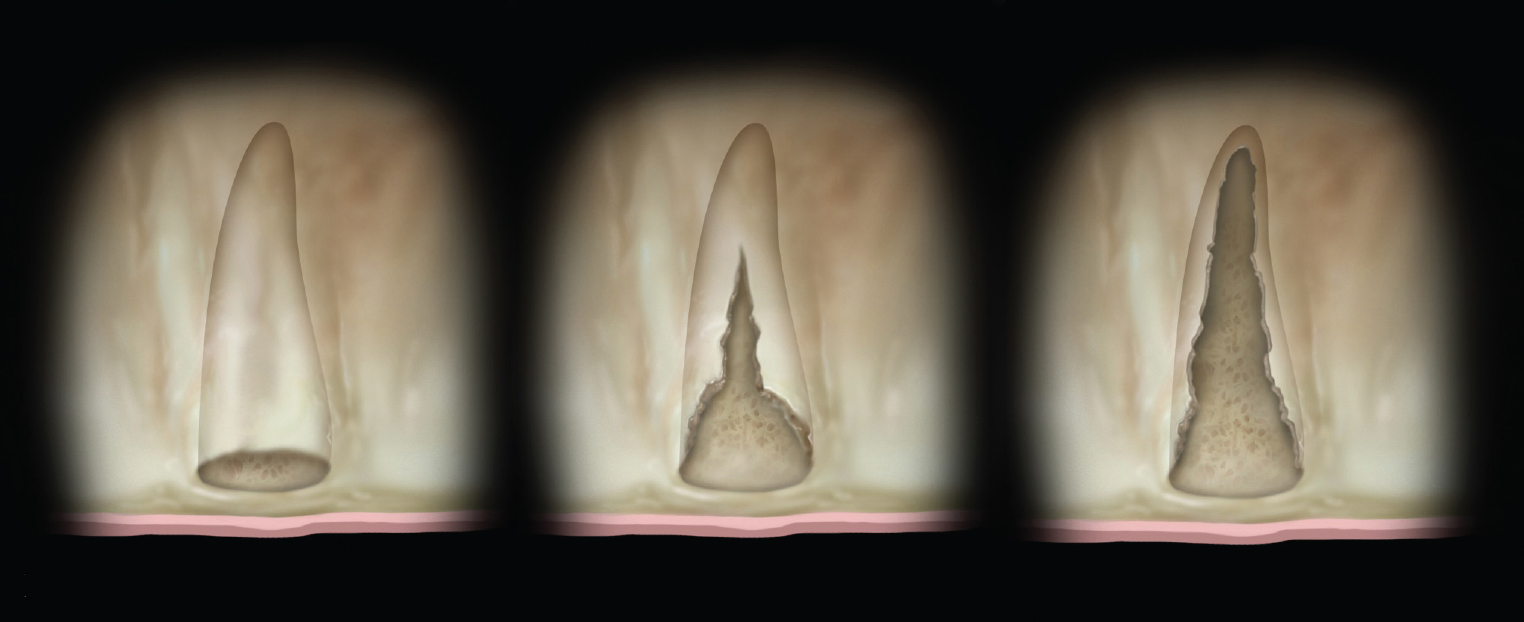

(Left) Grade I socket with an intact buccal plate demonstrating less than 25% bone loss; (Center) Grade II socket showing  ssure, dehiscence, and approximately 50% buccal plate loss; (Right) Grade III socket with more than 50% buccal plate loss.